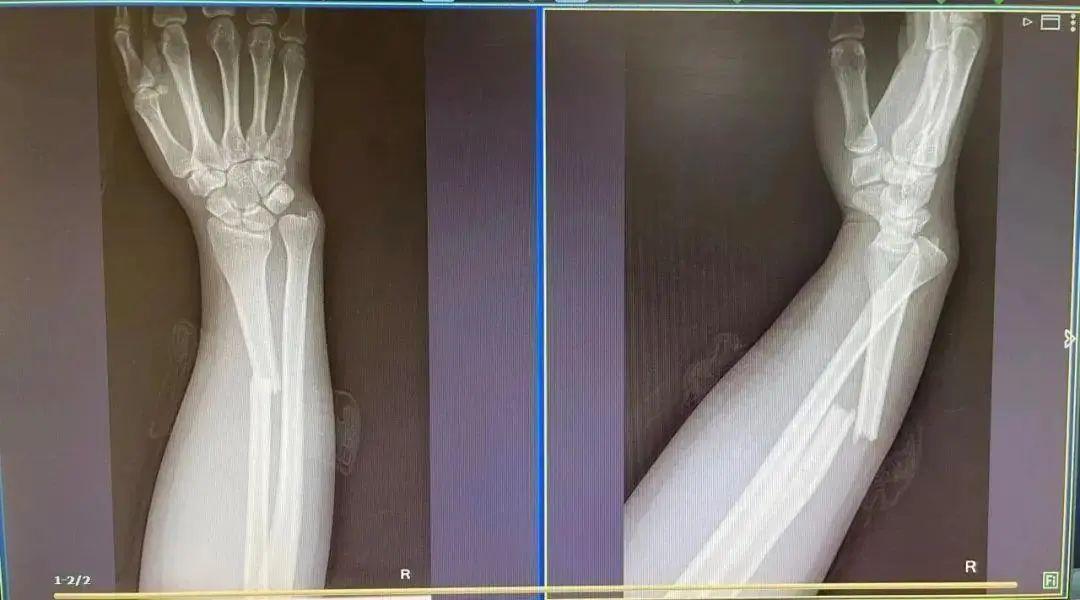

2019年,36歲的劉女士在出游時,與孩子一同坐在行李箱上“滑行”,不料兩人突然失去重心,摔倒在地,孩子臉部擦傷,劉女士手臂也骨折了。